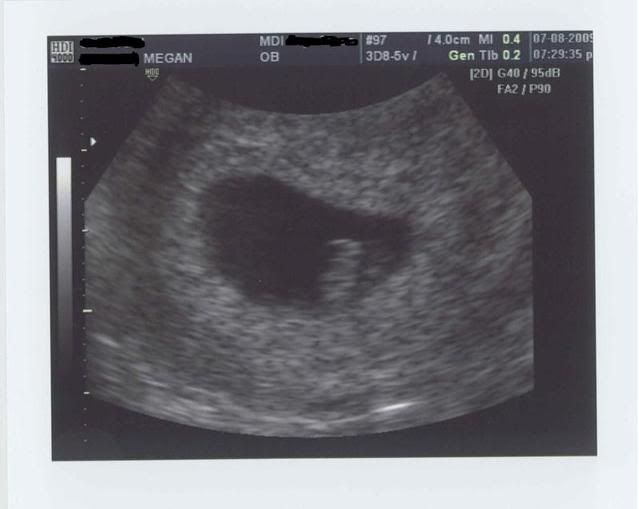

ladies, meet our gummi bear...

:-) Measuring right on track, and with a beautiful strong heartbeat (140bpm).

Thank you for all the support these past few days... I can't even tell you how amazing it was to see that little heart beating away. We are over the moon!